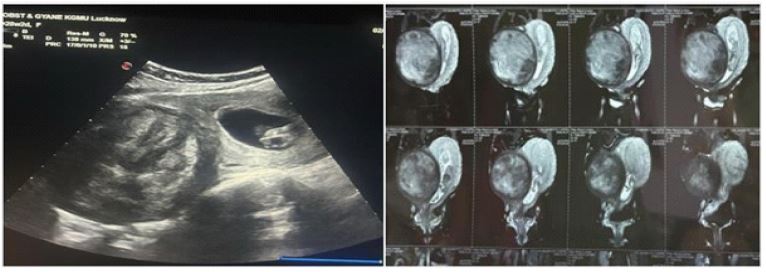

Figure 1: Ultrasonography and MRI film showing large subserosal uterine fibroid in relation to fetus.

All patients were admitted to hospital between 10-16 weeks of gestation for clinical evaluation, laboratory workup, transvaginal & abdominal ultrasonography and electrocardiography. Fibroid characteristics such as size, location, distance from the lower pole of the myoma to the uterine cavity, and presence of areas degeneration were studied (Figure 1). Doppler ultrasonography & MRI was further used to study vascularsupply and mapping of leiomyoma, when needed. Blood typing and cross matching was done. One unit of blood was readied as a precautionary measure to mitigate the risks associated with significant blood loss during surgery. Laparotomy was performed via midline vertical incision that extended over the umbilicus under regional anaesthesia (or endotracheal anaesthesia when needed), after ruling out congenital malformations & chromosomal anomalies. Myoma was enucleated via transverse incision given over fibroid capsule followed by blunt and sharp dissection. Following myomectomy reconstruction of uterine wall was done in double layer via polyglactin no.1-0 suture material (Figure 2). Haemostasis was achieved via multiple sutures at myoma base. In postoperative period tocolytics were given to prevent uterine contrac tions. Intravenous Isoxsuprine Hydrochloride drip was started intraoperatively and continued for 48 hours which was then tapered and patient put on oral medication for 1 week. Progesterone support in form of Hydroxyprogesterone Hexanoate 500 mg given intramuscularly before surgery and every week till 36 weeks to prevent possible miscarriage and preterm labour. All patients were given antibiotics and analgesics for 5 days postoperatively. Fetal well being was checked by ultrasonography at the end of surgery. Removed myoma was sent for histopathological examination. After discharge patient were closely followed up every 2 weekly for antenatal surveillance on OPD basis. Ultrasonography was performed monthly to monitor fetal growth. Maternal and fetal outcomes & complications were studied.